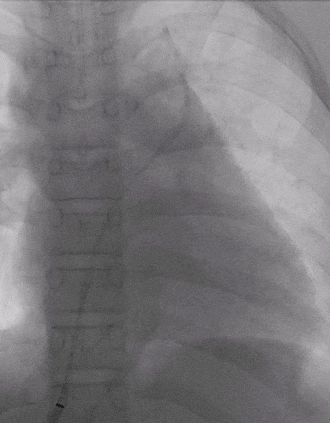

术后复查

术后复查胸片

术后复查心电图,无房室传导阻滞